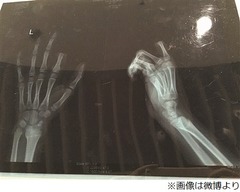

すると、その後の食事のさいに悲劇が起きる。小朋くんと母親のやり取りを耳にしていた父親が小朋くんを叱ったところ、突然手にしていたフォークを離し、自分の後方の机の上に置かれていた包丁で自ら指を切断。刃は左手の人差し指第二関節あたりに落とされたという。

目の前で発生したこの出来事に両親は茫然自失となったが、我に返るとすぐに切断された指を包み、小朋くんを病院に連れて行くことに。3時間以上にも及ぶ接合手術が行われることになった。

医師によれば、手術は一応成功したものの、一週間程度は回復状況の確認が必要で、今後の生活に支障をきたすことになるのかどうかは、そのときにならないとわからないという。